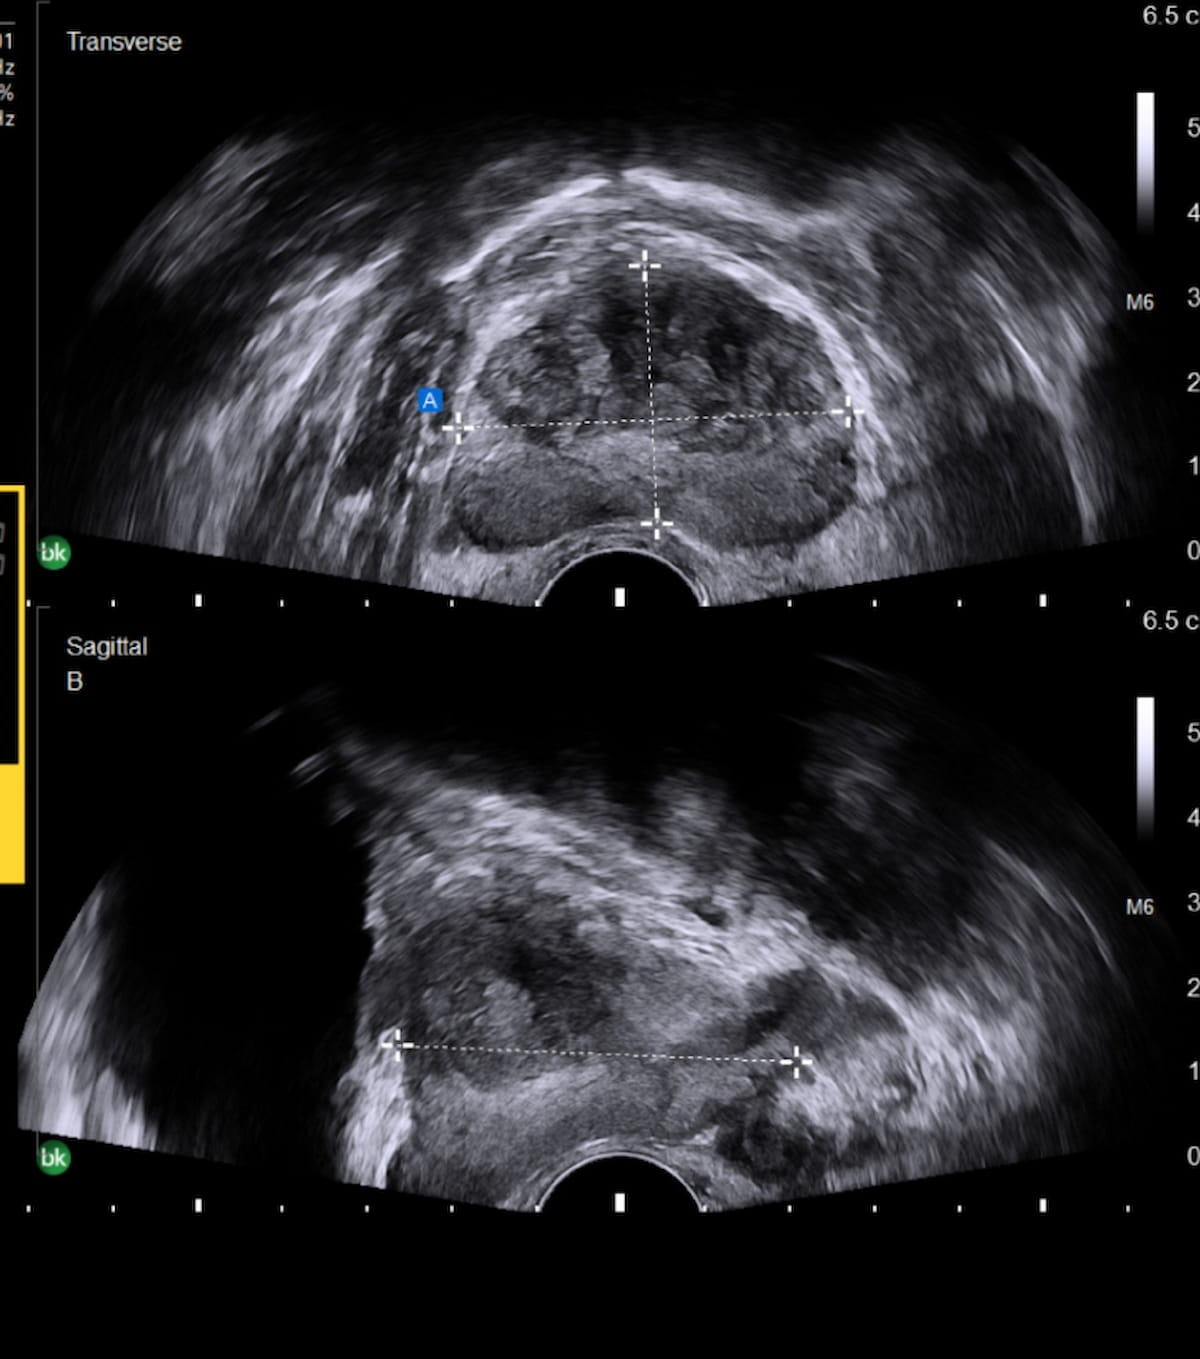

In a comparison of image-to-text large language models (LLMs), ChatGPT 4.0 offered a 95 percent sensitivity rate and an 83 percent AUC that were comparable to that of two senior radiologists and one junior radiologist interacting with LLM to differentiate between malignant and benign thyroid nodules on ultrasound.